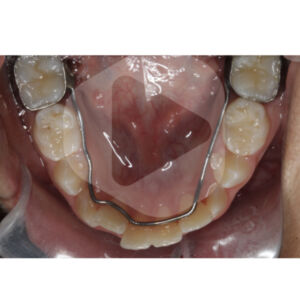

Para manter esse espaço normalmente utilizamos um arco lingual. Mas também poderia ser uma placa removível, por exemplo, desde que o paciente realmente use adequadamente durante o período de troca dos dentes posteriores.

Considerando que estamos falando do arco inferior e que o segundo molar decíduo é o último dente a esfoliar no arco, o arco lingual não precisa ser instalado no momento que realizamos a análise. O momento de instalar o arco lingual é logo antes de esfoliar o segundo molar decíduo.

Na prática, costumo instalar o arco lingual assim que esfolia o primeiro molar decíduo ou quando observo a mobilidade do segundo molar decíduo e não antes disso. Considere que após a esfoliação do primeiro molar decíduo você ainda terá aproximadamente 6 meses para esfoliar o segundo molar decíduo e portanto, terá um tempo para instalar o arco lingual. Portanto, nessa fase da dentição, não deixe de acompanhar o paciente a cada 6 meses aproximadamente, pois assim você não perderá o ‘time’ para instalar o arco lingual a tempo de reservar o espaço na troca dos dentes posteriores.

Vou colocar aqui as imagens de um paciente com discrepância de modelo igual a ZERO em que o único procedimento interceptivo realizado no arco inferior foi a instalação de um arco lingual no segundo período transitório da dentição mista.